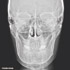

Höchste Bildqualität

X-ERA SMART verfügt über ein einzigartiges Patientenpositionierungssystem im 3D Bereich, das jede Bildverzerrung durch Patientenbewegung komplett ausschließt. Das Technologiekonzept erzeugt eine Bildqualität in extrem hoher Auflösung. Zwei verschiedene Aufnahmegrößen mit einer Voxel Größe von 80μm / 100 μm liefern in jeder Sichtfeldgröße (FoV) exzellente Ergebnisse für die weitere Diagnostik und Behandlung.

Nacholgend ein paar phänomenale Bilder & Werte,

die nicht nur einem Fachmann die Sprache verschlagen:

Aufnahmeparameter: Ceph LA; 82 kV; 10 mA; 8.0 s; 0.8 mm CU + 6.0 mm AL

gemessene Dosis: 2.99 µGy